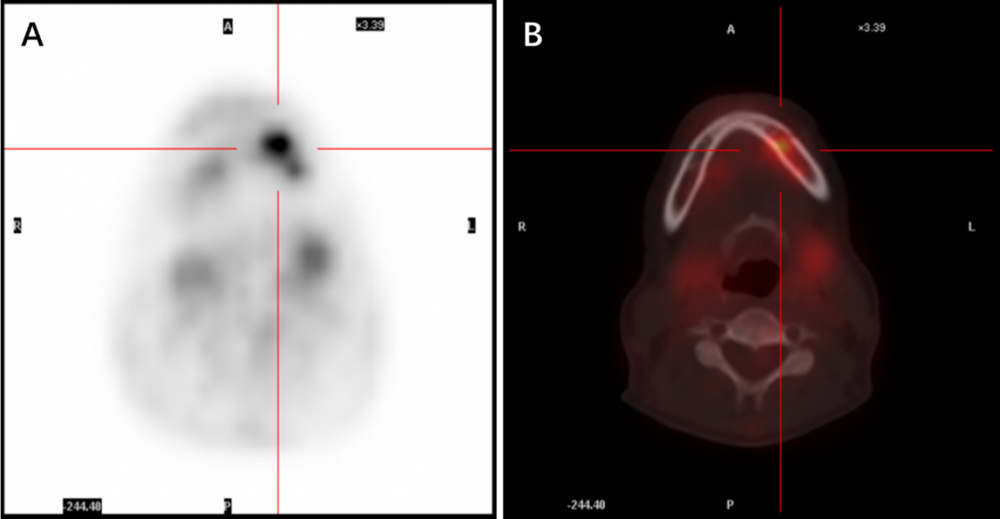

患者女性,52 歲,反復發(fā)熱 1 個多月,最高體溫 38.8℃,伴有畏寒。患者感到左下頜骨麻木,左牙齒輕微疼痛。血常規(guī)正常,C 反應蛋白(CRP)7.33 mg/L,紅細胞沉降率(ESR)42 mm/h,類風濕因子 5.7 IU/mL,抗 O 89 IU/ml,抗核抗體、甲功、EBV、CMV-DNA、腫瘤標志物均陰性。頭顱(包括下頜骨)、胸部、腹部 CT 未見活動性病變,心超正常?;颊呷朐呵安?PET-CT,顯示下頜骨左支牙槽葡糖糖代謝增高(SUV max=5.87)(圖 1)。雙肺多發(fā)小結(jié)節(jié),雙肺下葉滲出性改變,脾腫大,考慮感染可能。

圖 1. 患者入院前 PET-CT 結(jié)果